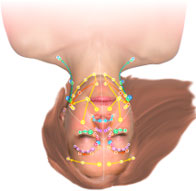

What is MLD?

Manual Lymphatic drainage is a pleasant and powerful therapeutic technique for conditions ranging from acne to lymphedema.

VodderMLD.com is a website dedicated to teaching the only proven effective method of Manual Lymph Drainage for the treatment of over 60 pathologies including lymphedema. The Vodder technique prevents lymphedema in proven studies.